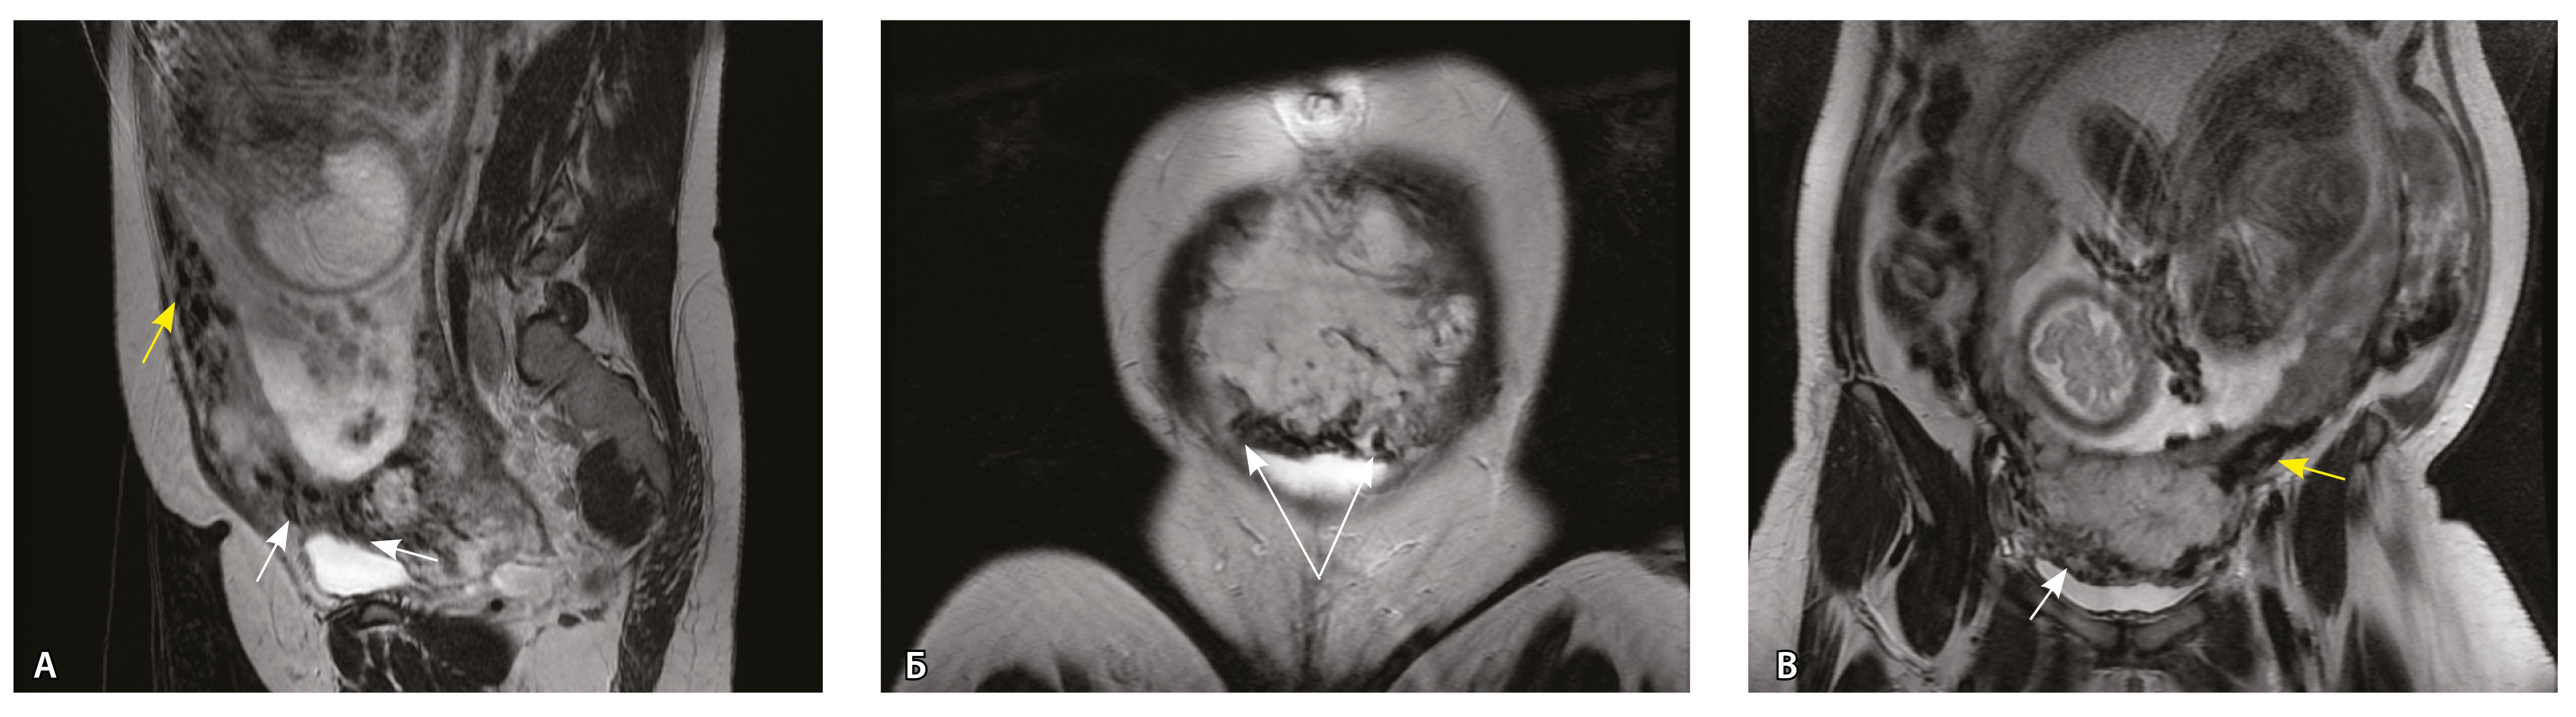

Сосуды 5-го типа. Наличие гиперваскуляризации за пределами матки по данным МРТ, на границе с мочевым пузырем с вовлечением его стенки, сосуды в области перешейка матки, параметрия, в том числе в сочетании с признаками фиброза, наличием рубцово-спаечных изменений и др. Можно предположить, что сосуды 5-го типа являются аналогом pl. рercreta PAS 3b, 3c (рис. 15).

Рис. 15. Беременность 34 недели, pl. percreta, PAS 3b по FIGO (A, Б), PAS 3c по FIGO (В). На магнитно-резонансных томограммах в режиме Т2-взвешенного изображения в сагиттальной (A, В) и аксиальной (Б) плоскостях определяется гиперваскуляризация в области выраженно истонченного нижнего маточного сегмента с распространением сосудов на заднюю стенку мочевого пузыря в области дна (белые стрелки), в область перешейка матки (желтые стрелки)

Данный вариант в патоморфологической картине наиболее сложен для оценки ввиду того, что такие структуры, как параметрий, перешеек матки, стенка мочевого пузыря, обычно не предоставляются в виде макропрепаратов, поэтому визуальные методы, в частности МРТ, могут с большей точностью оценить вовлеченность смежных структур. На микропрепаратах данный вариант инвазии плаценты сочетается с рубцово-спаечными изменениями задней стенки мочевого пузыря с нижним маточным сегментом (рис. 16).